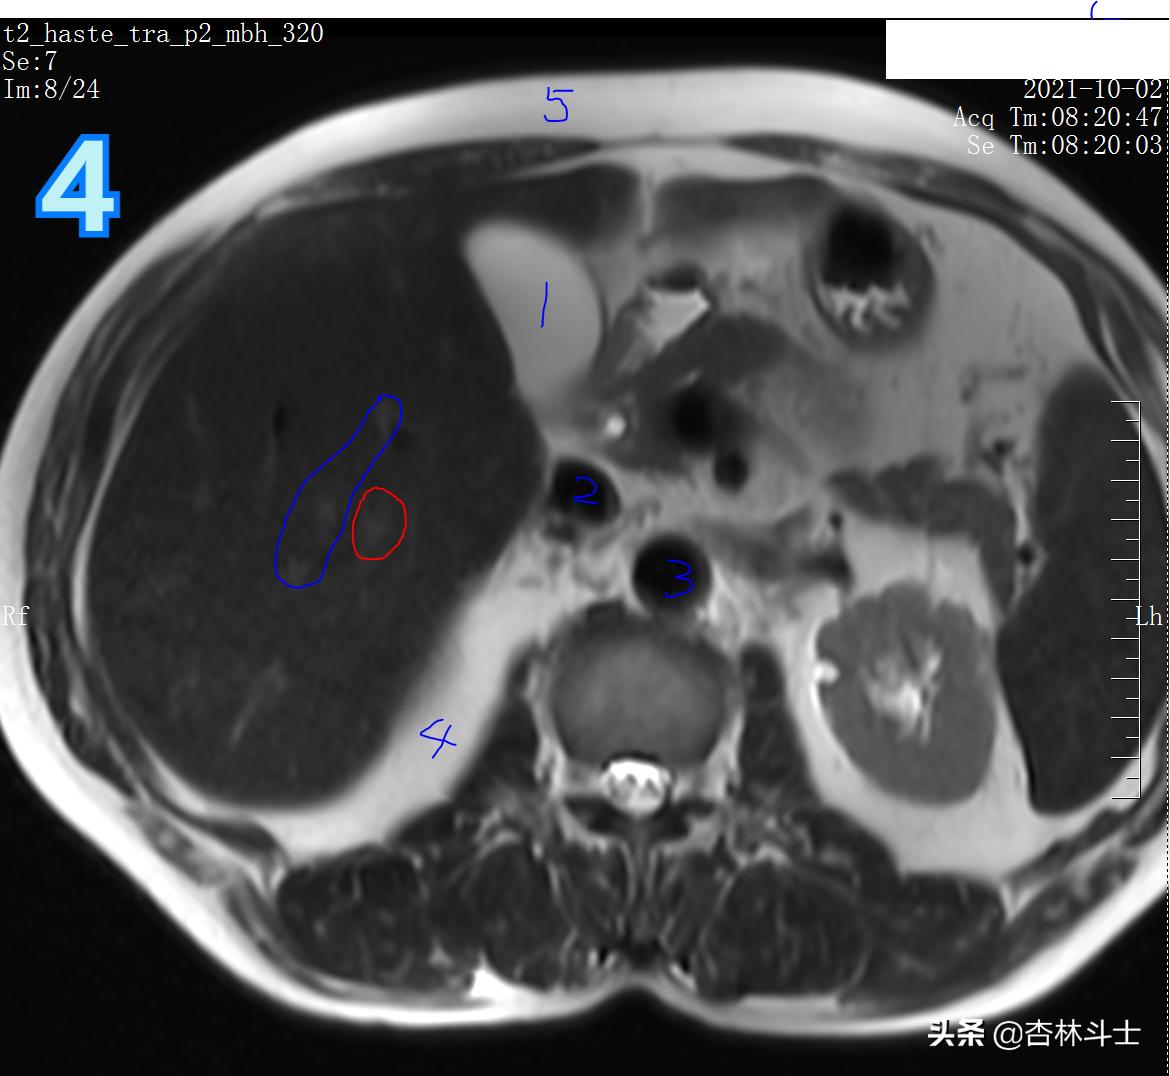

图4 T2加权像

图4 蓝色框为三支肝内血管 红框内为新发病灶呈高信号。1、胆囊 2、下腔静脉 3、腹主动脉 4、腹部器官间脂肪组织 5、皮下脂肪